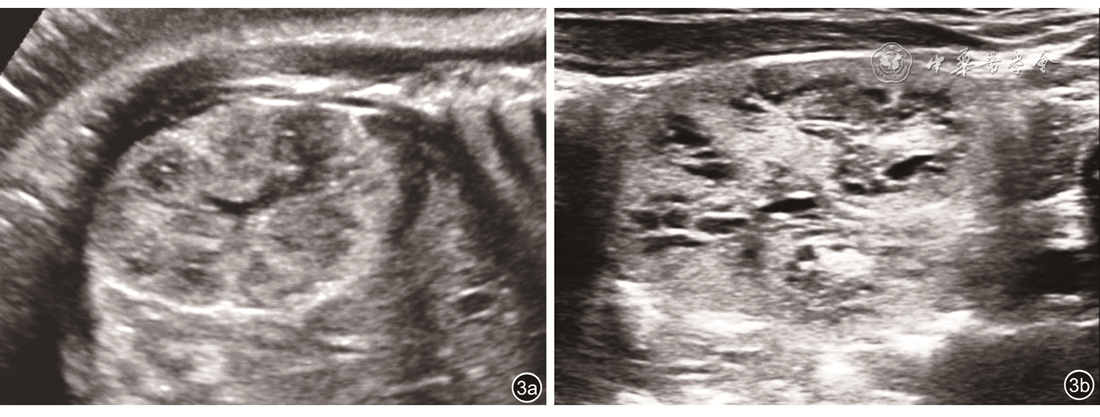

图2 孕36周胎儿肾超声声像图。双侧肾回声增强,皮髓质分界清晰,髓质回声低于皮质回声

注:RK为右肾

图3 孕38周胎儿肾超声声像图。双侧肾回声增强,皮髓质分界清晰,髓质扩张并囊性变。图a为产前声像图,图b为产后声像图,产前产后声像图表现一致。取脐带血行染色体核型分析未见异常

图4 孕28周胎儿肾超声声像图。双肾横切面显示体积明显增大,回声增强,皮髓质回声倒置,髓质回声高于皮质回声。基因检测为PKHD1基因突变